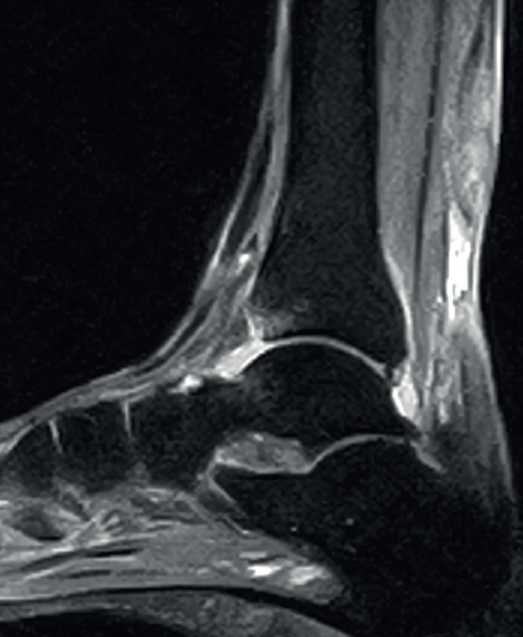

The normal Achilles tendon is observed as a hypointense structure in both T1- and T2-weighted sequences(33)(Figure 3). In the sagittal plane its margins are parallel, and in the axial plane its distal portion presents an anterior concave margin towards the calcaneus over most of its course. The thickness is similar along its trajectory, and a minimum amount of fluid is observed at retrocalcaneal level (fluid surrounding the tendon is pathological)(34).

Figure 3. Magnetic resonance imaging view of ankle (T1 sequencing). Sagittal view showing a normal tendon.